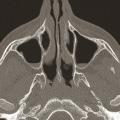

L’imagerie est inutile pour le diagnostic d’une rhinosinusite aiguë simple.1 En effet, la spécificité des signes tomodensitométriques n’est pas bonne, en particulier pendant la saison froide et chez les jeunes enfants. La constatation d’une opacité d’un sinus, d’un niveau liquide (fig. 1 ) ou d’un épaississement de la muqueuse (supérieur à 4 mm) [fig. 2 ] ne suffit pas au diagnostic de rhinosinusite et rend compte d’un grand nombre de traitements par excès.

L’imagerie est inutile pour le diagnostic d’une rhinosinusite aiguë simple.1 En effet, la spécificité des signes tomodensitométriques n’est pas bonne, en particulier pendant la saison froide et chez les jeunes enfants. La constatation d’une opacité d’un sinus, d’un niveau liquide (